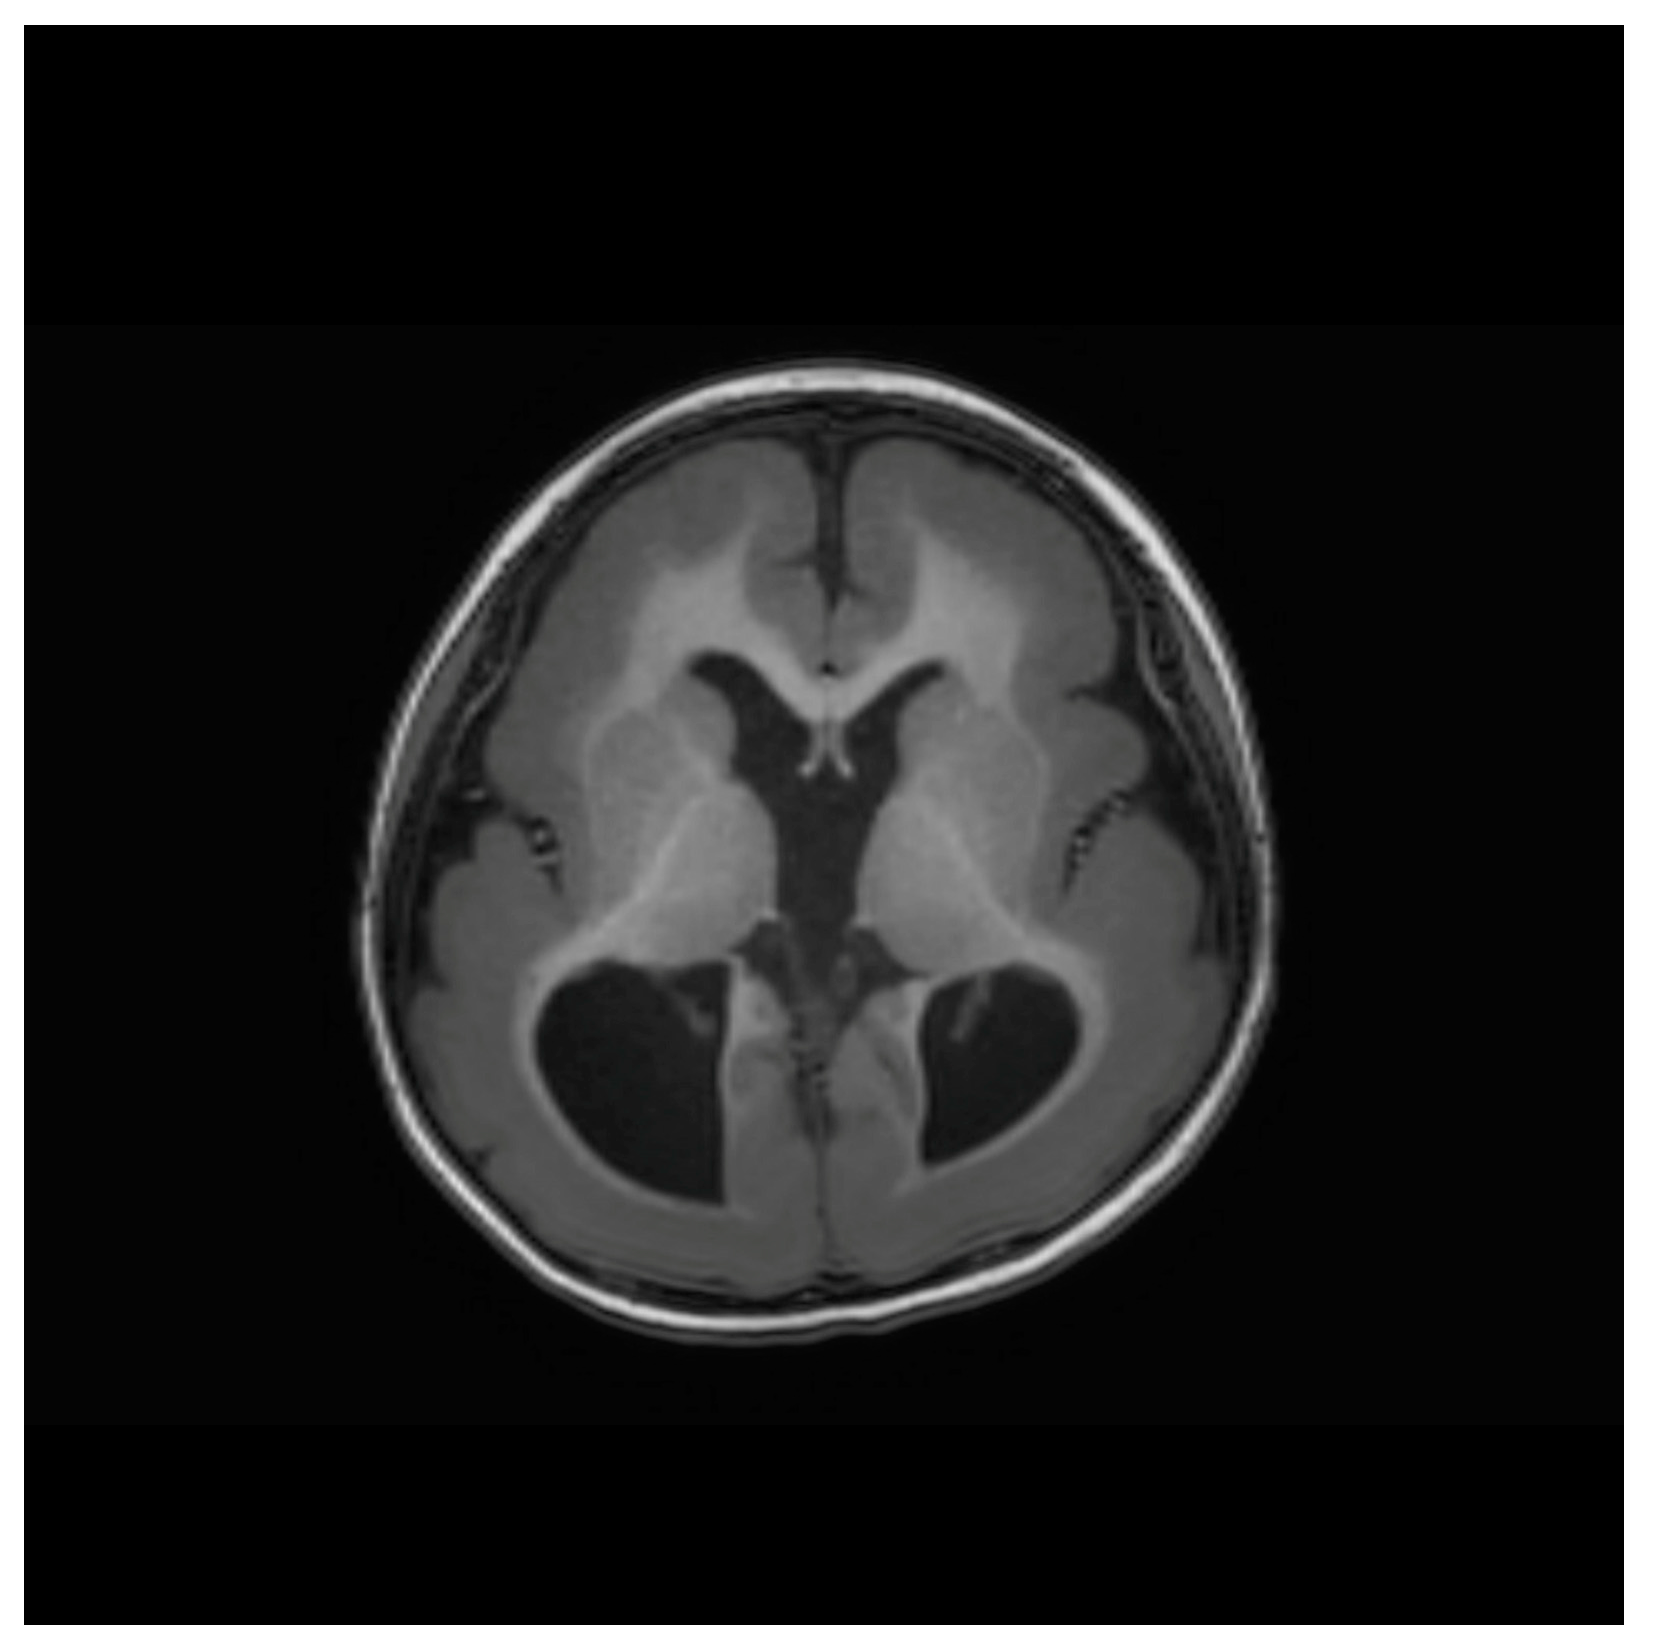

A 4-year-old girl (height, 95 cm; weight, 14 kg) previously diagnosed with Miller–Dieker syndrome was scheduled for intermittent exotropia surgery. A female infant (weighing 2510 g (23rd percentile), with a head circumference of 31 cm (9th percentile) and height of 47.5 cm (49th percentile)) was born at 37 weeks of gestation via cesarean section. Head ultrasonography showed ventriculomegaly, and brain magnetic resonance imaging revealed lissencephaly (Figure 1). A gene study confirmed a lissencephaly type 1 mutation, indicating a deletion in chromosome 17p13.3, including the PAFAH1B1 gene. Neonatal echocardiography showed a patent foramen ovale, which is a type of atrial septal defect. No other congenital anomalies were noted. Preoperative echocardiography showed patent foramen ovale occlusion. She developed a generalized tonic–clonic seizure from four months of age and was started on anticonvulsants (valproic acid and levetiracetam). She has been seizure-free since experiencing her last seizure a year before surgery.

Figure 1. Brain magnetic resonance image (MRI) showing lissencephaly.